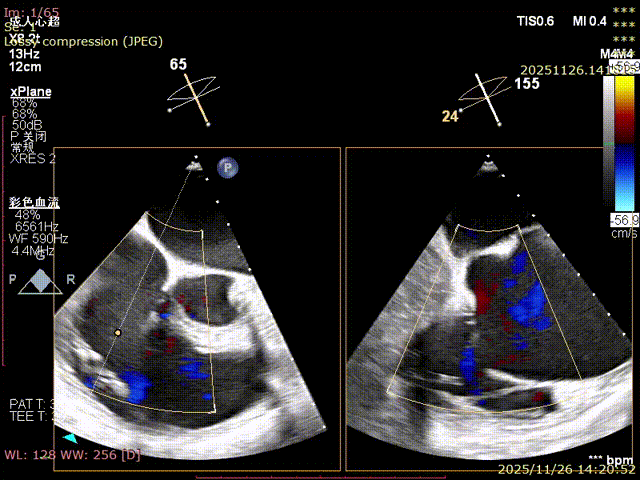

Echocardiography Findings: Severe tricuspid regurgitation (4+), with regurgitation jets primarily located at the postero-septal and central regions. The tricuspid annulus is dilated (annulus diameter: 42 mm).

Preoperative

Regurgitation: 4+

Postoperative

Mild regurgitation (1+)